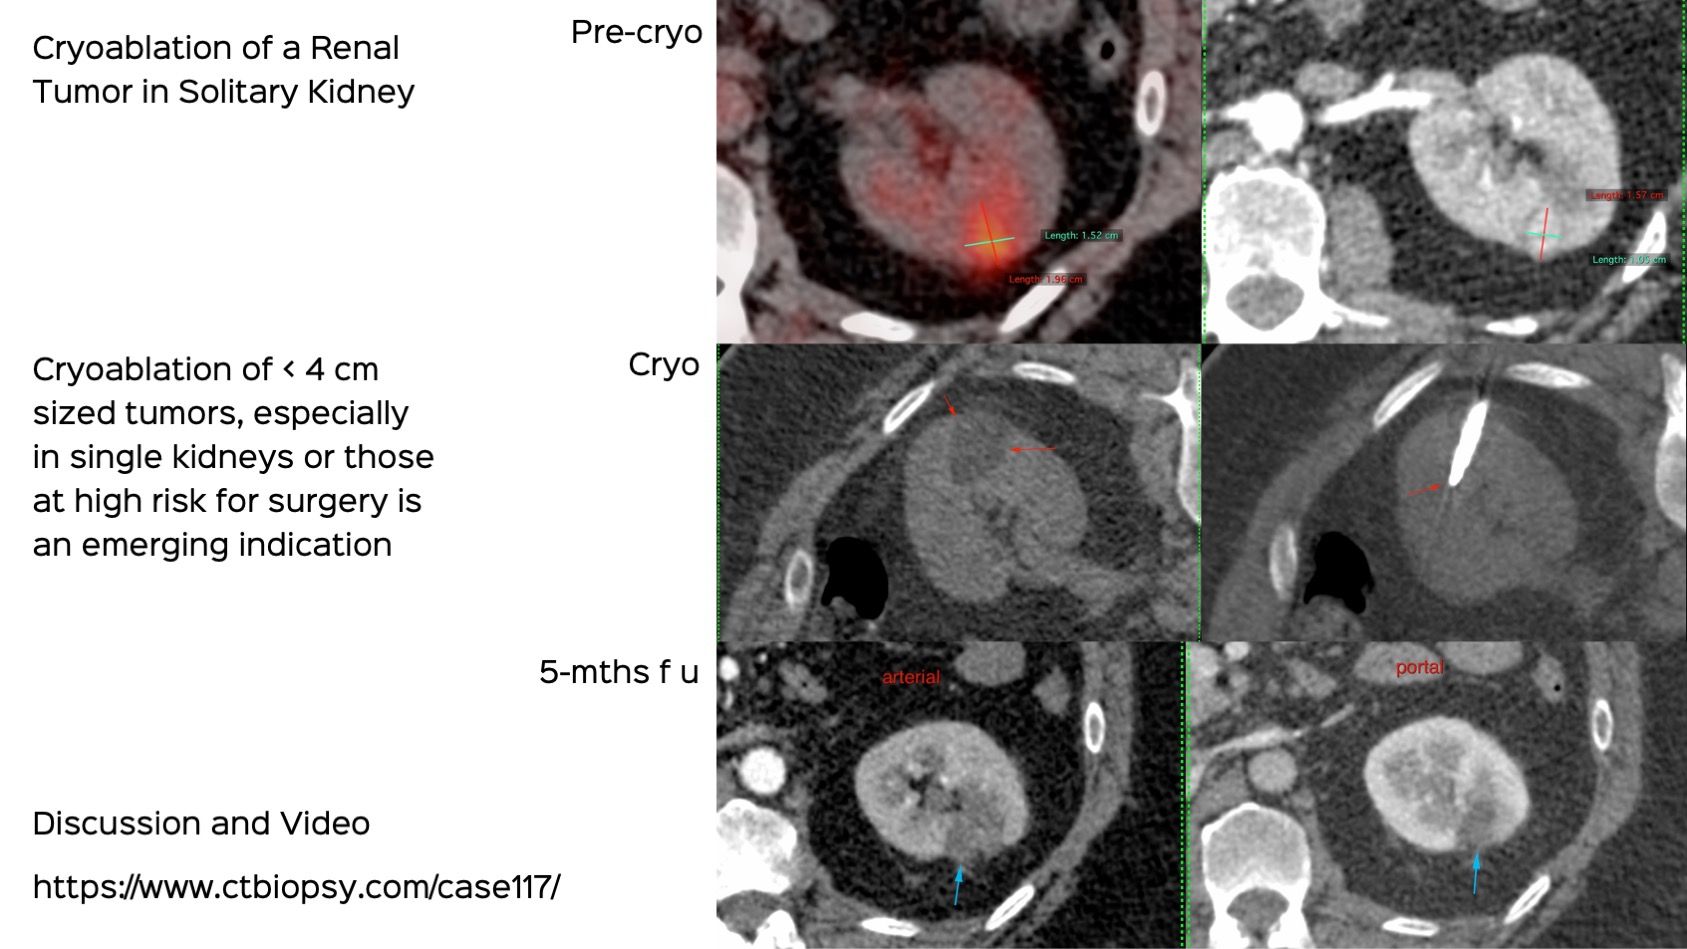

Case 117: Cryoablation of a Small Renal Tumor in a Solitary Kidney